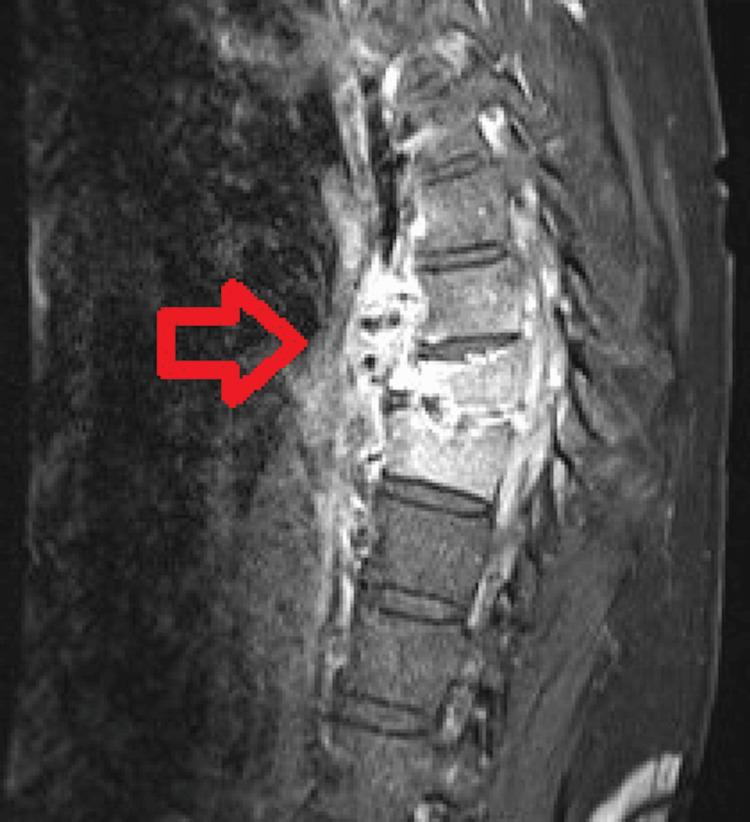

Vertebral (spinal) osteomyelitis is a rare spinal infection of the vertebral column that can be caused by bacteria or fungi. Though the initial treatment for all patients with vertebral osteomyelitis consists of antibiotics, surgery can be indicated in certain cases, such as in the presence of spinal instability or when antibiotics are not successfully eliminating the infection. Achieving spinal stability can be an important component of treating fracture-related infections, as instability can cause local damage and disrupt the healing process. The authors present the case of a patient with vertebral osteomyelitis that was not resolving with the administration of antibiotics in the context of a spinal fracture. A minimally invasive surgery was performed to achieve spinal stability and the infection soon resolved with antibiotics.

脊椎骨髓炎是一种罕见的脊柱感染疾病,可由细菌或真菌引起。虽然所有脊椎骨髓炎患者的初始治疗都包括使用抗生素,但在某些情况下,如存在脊柱不稳定或抗生素未能成功消除感染时,可能需要进行手术。实现脊柱稳定是治疗骨折相关感染的重要组成部分,因为不稳定会导致局部损伤并干扰愈合过程。作者介绍了一例脊椎骨髓炎患者的病例,该患者在脊柱骨折的情况下使用抗生素治疗后病情未得到缓解。通过微创手术实现了脊柱稳定,随后感染在使用抗生素后很快得到解决。